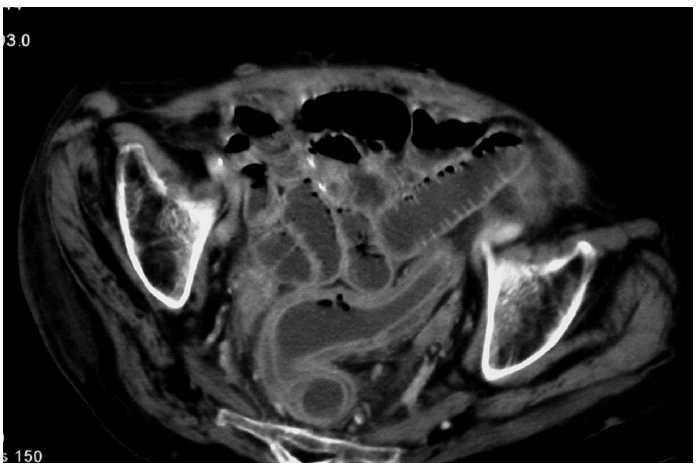

Paciente de 72 años con factores de riesgo cardiovascular, intervenida de urgencia por perforación intestinal y peritonitis, secundaria a obstrucción intestinal por adherencias. Se realiza resección intestinal y adherensiólisis. Durante el postoperatorio se mantiene antibioterapia de amplio espectro por vía intravenosa; presenta deposiciones diarreicas y en el 14.o día, dolor y distensión abdominal. La tomografía computarizada de abdomen (fig. 1 y 2) es compatible con colitis isquémica de colon izquierdo y recto, con neumatosis intestinal. Analíticamente, no presentaba alteraciones indicativas de isquemia intestinal, salvo leucocitosis en ascenso. Ante la sospecha de colitis seudomembranosa, se solicita detección de toxina de Clostridium difficile en heces, que es positiva; se resolvió el cuadro con metronidazol por vía oral.

Fig. 2.